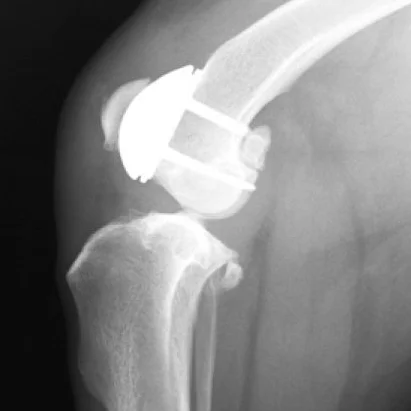

KYON PGR – Patellar Groove Replacement

The PGR device is a unique solution to address the condition of patellar luxation where the kneecap dislocates from its normal location in the patellar groove. It is the first and only device on the market to restore a functional patellar groove.

Patello-femoral degenerative joint disease is a frequent, often ignored consequence of some of the most common conditions of the canine stifle such as patellar luxation or cruciate ligament degeneration and rupture. Surgical treatments of patellar luxation, whether by tibial tuberosity transposition or by corrective osteotomies of the femur and/or tibia combined with patellar groove deepening by one of several methods, seek restoration of joint stability.

The PGR implant provides:

Immediate stability of patella in a smooth artificial groove to prevent luxation

Easy and secure fixation by a two component design consisting of a base plate and an artificial groove

Low friction ensured by a smooth Amorphous Diamond-Like Carbon (ADLC) coated groove surface with very low coefficient of friction (m=0.05 on steel), offering the possibility of maintaining heat generation below the threshold of thermal necrosis.

Rapid bone ingrowth of the baseplate facilitated by BioCer® surface treatment

More than 10 different sizes to ensure ideal fit for every dog breed

Ostectomy of the patellar groove just cranially to the insertion of the tendon of the long digital extensor creates a broad, well perfused cancellous bone bed onto which the base plate is secured by titanium bone screws. The groove component is then attached to the base plate by means of three conical pegs fitted into receiving conical holes. The broad area of the ostectomy of the patellar groove allows for considerable freedom in medial-lateral positioning of the base plate that can be used to improve quadriceps-to-patellar tendon alignment, thus avoiding conventional tibial tuberosity transposition. Use of trial implants during surgery aids the search for an optimal position of the final implant.

Functional loading of the implant leads to compression of its interface to the bone, which is mechanically favorable to the ill-conditioned load transfer called for by conventional tuberosity transposition, where the full force of the patellar tendon is transferred to the tibia by pins and a figure eight wire.

Significant angular deformities can be treated by concurrent corrective osteotomies in addition to patellar groove replacement should the condition of the patello-femoral joint call for it. The same is true for cruciate ligament ruptures that can be concurrently treated by, for example, Tibial Tuberosity Advancement (TTA).